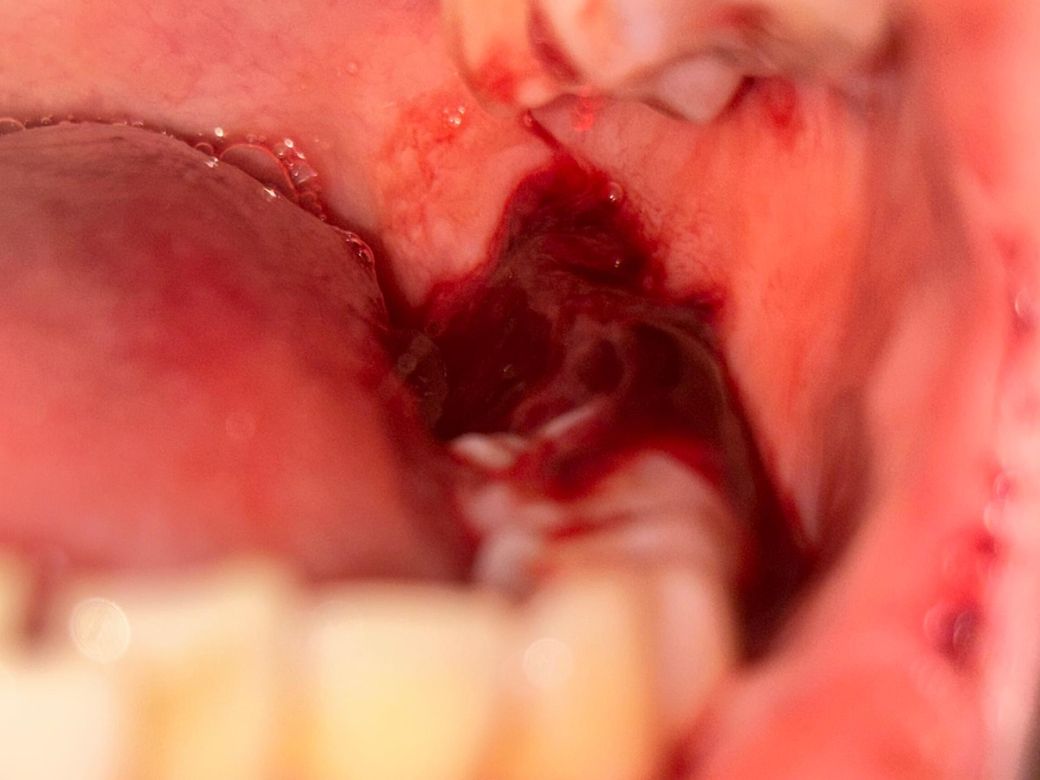

사랑니 발치 후 피 응어리 생겼는데요.

사랑니 발치를 4시쯤에 하고 2시간 반쯤 거즈 물었는데요.

거즈 빼고 나서 몇 시간 있다가 확인해보니 엄청 많이 피가 응어리 졌는데 어떡하죠? 집에 거즈도 없고, 약국도 다 닫았는데 혹시 심각한 건 아니겠죠?

• 1번 째 사진